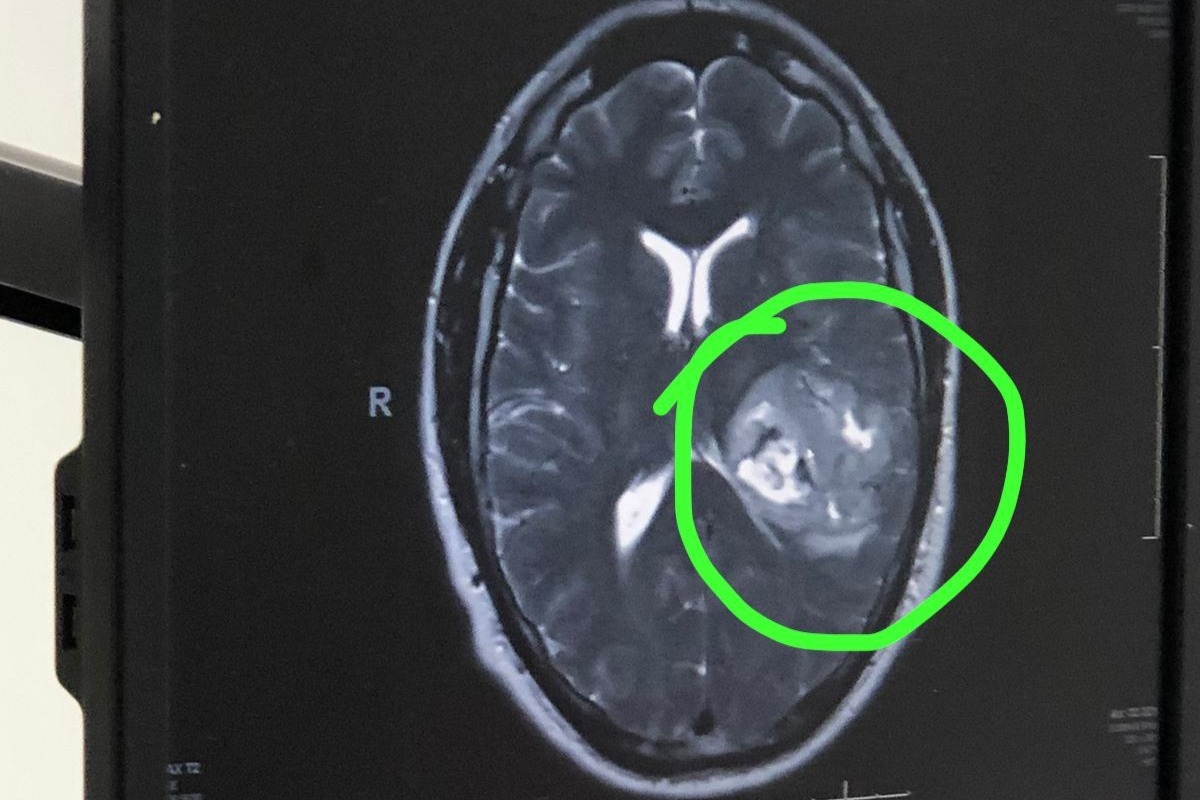

Mi esposo Vitico (Victor) hace unos días empezó ha tener momentos en los que se le enredaba la lengua, esto fue empeorando y decidió ir al médico el 23 de Enero con un fuerte dolor de cabeza y la tensión alta. El Doctor al realizarle un examen de preguntas y ver su poca capacidad para responder correctamente, lo refirió al hospital por emergencia para hacerle una tomografía; al recibir los resultados empezó esta pesadilla que estamos viviendo... Mi esposo tenía un tumor en su cerebro y debía ser operado de urgencia .

Mientras esperaba hospitalizado que se realizara todo el procedimiento para la operación pautada el martes 28 de Enero, el deterioro de su cerebro fue avanzando muy rápido y el lunes 27 de Enero al final de la tarde se levantó de la cama y se empezó a desvanecer, seguido de una parálisis de todo su lado derecho del cuerpo y nos repetía “me duele la cabeza”, “me duele mucho la cabeza” y empezó a convulsionar .... El tumor habia derramado sangre dentro de su cerebro.

My husband Vitico (Victor) a few days ago started having moments where his tongue was getting tangled when he spoke, he decided to go to the doctor when his symptoms got worse. On January 23 he went to the doctors with a bad headache and high blood pressure. The doctor examined him with a few questions and noticing he couldn’t respond correctly sent him to the ER for an MRI, when we received the results our worst nightmare began. We were told that my husband had a tumor and that he needed surgery immediately.

We were admitted to the hospital and were told that he needed to be prepared for surgery and it would take place on Tuesday January 28, his symptoms were getting worse and on Monday evening January 27 he stood up from bed and fainted, followed by him being paralyzed on his right side and repeating his head was hurting and started having a seizure....

He was having a brain hemorrhage.